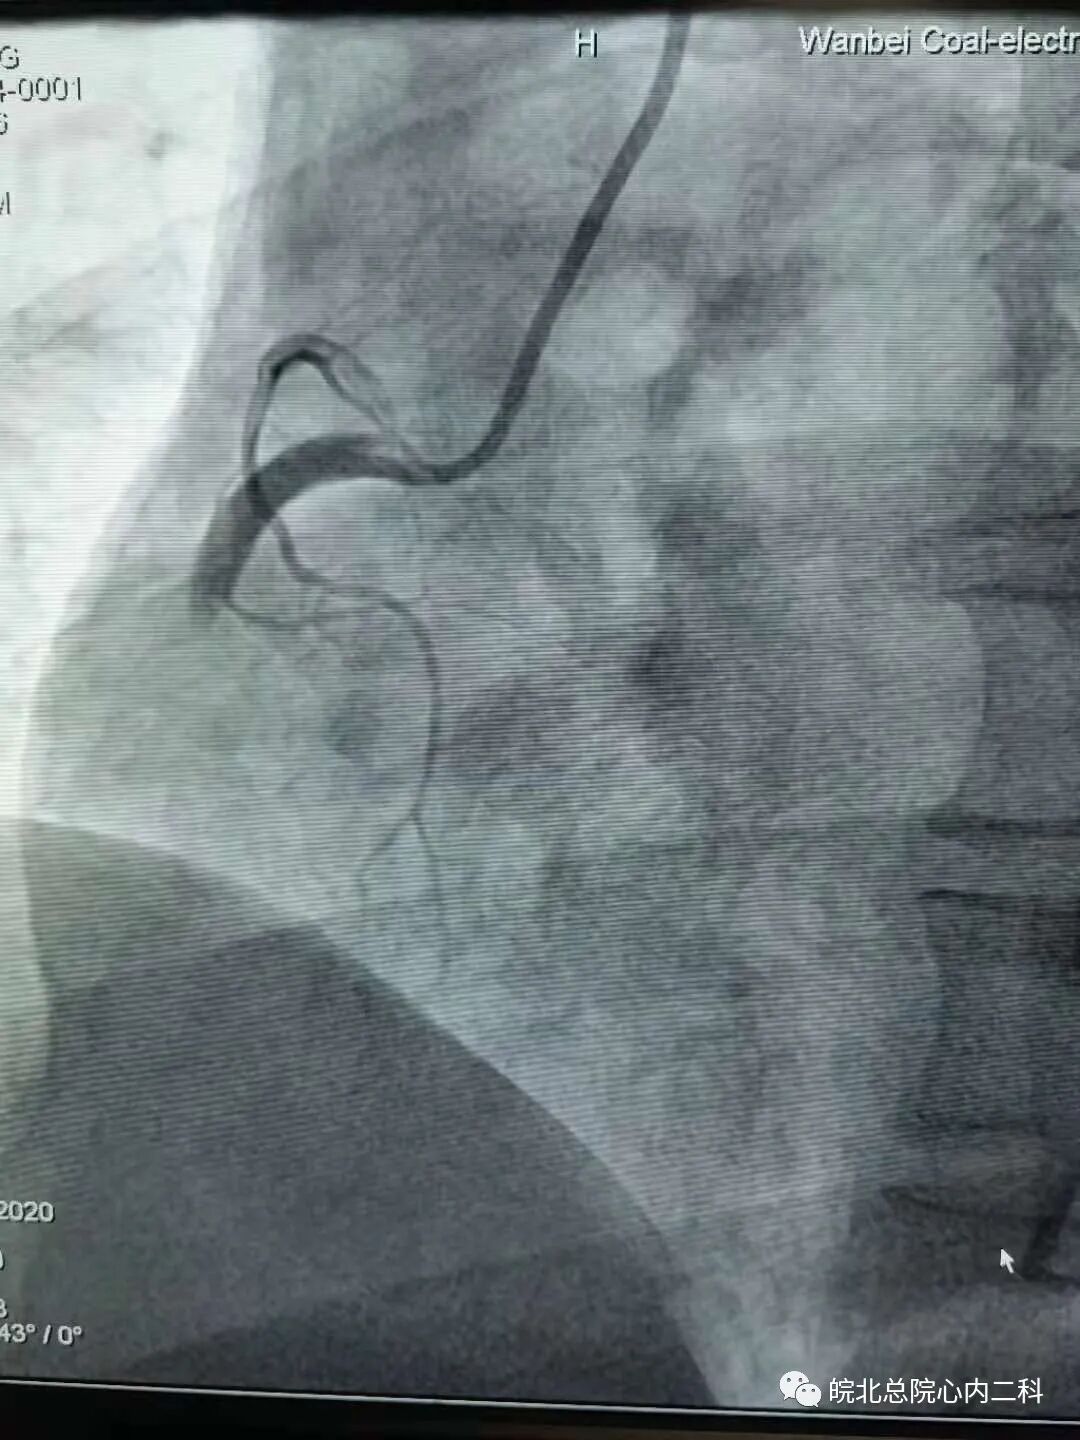

昨日皖北总院心内二科连续抢救两名急性下壁ST段抬高型心肌梗死患者,两名患者均以最短的时间接受了急诊介入治疗,其中一名患者35岁,打篮球后突发胸痛1小时入院,患者直接绕行病房,急诊冠脉造影右冠近中段完全闭塞。崔主任手术团队十分钟导丝通过开通血管,最快的挽救患者的存活心肌,改善患者的预后!目前两位患者生命体征尚平稳,近期可康复出院!